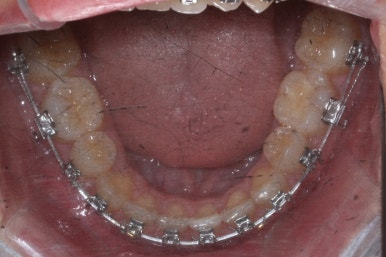

부산교정전문의 키다리아저씨치과에 처음 내원하셨을 때 당시의 입안 모습입니다.

윗니 뿐만 아니라 아랫니 부위에도 덧니가 관찰됩니다. 다른 앞니, 어금니 부위도 약간 삐뚤한 부분이 보입니다.